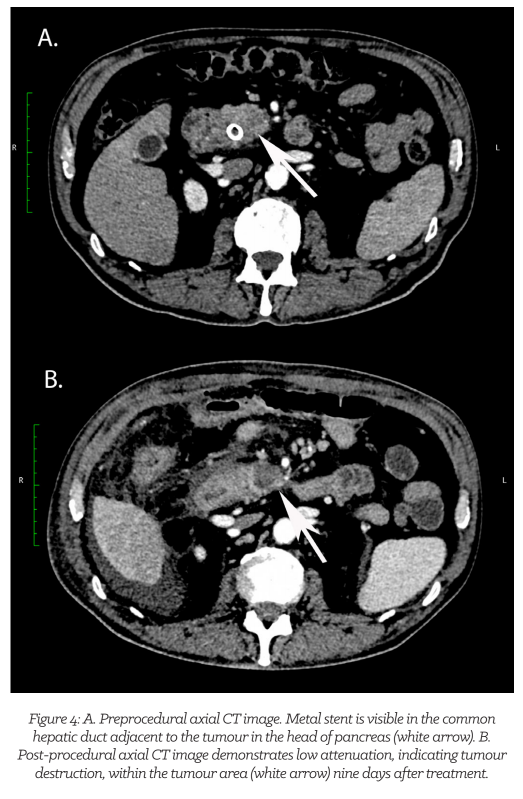

A CT image showing tumour destruction after performing imILT procedure